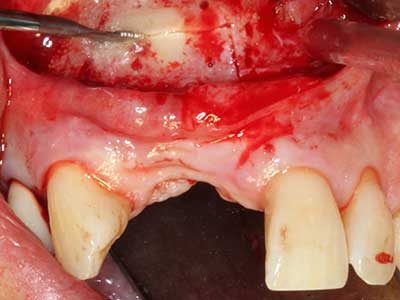

Si es preciso realizar intervenciones quirúrgicas en las que el hueso está en contacto directo con estructuras sensibles, como son los vasos sanguíneos o los nervios, los instrumentos rotativos presentan un enorme potencial de provocar lesiones iatrogénicas. Así, precisamente en la representación de nervios después de una lesión iatrogénica, o en el transcurso de la lateralización de un nervio para resecciones, reconstrucciones o incorporación de implantes, los equipos piezoeléctricos pueden resultar muy útiles para preparar la tapa ósea y retirar las partes de tejido duro cercanas al nervio (fig. 17-20). Por lo general, un ligero contacto del cordón nervioso con el inserto piezoeléctrico no tiene consecuencia alguna; ahora bien, un procedimiento poco cuidadoso con movimientos tipo sierra o piezas de trabajo sobre la base ósea aún existente puede provocar lesiones nerviosas temporales o incluso permanentes. Con todo, el riesgo de sufrir una lesión de este tipo se considera significativamente inferior que en los casos en los que se utilizan sierras y fresas (Pereira, Gealh et al. 2014).